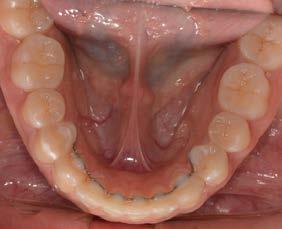

Caso clínico: paciente femenino de 19 años, patrón dolicofacial, perfil convexo, clase II esqueletal debido a una retrusión mandibular, mordida abierta anterior esqueletal, clase II molar, clase canina no establecida por mordida abierta, apiñamiento severo superior e inferior y deglución atípica.

Resultados: obtención de una clase canina I y clase molar II funcional, se corrigieron las sobremordidas horizontal y vertical, y se logró la coincidencia de líneas medias facial y dental. El manejo de la mordida abierta anterior se llevó a cabo por medio de la corrección del hábito de deglución atípica con la ayuda de spikes de resina, elásticos intermaxilares y arcos utility, y se obtuvieron buenos resultados estéticos, dentales y funcionales.